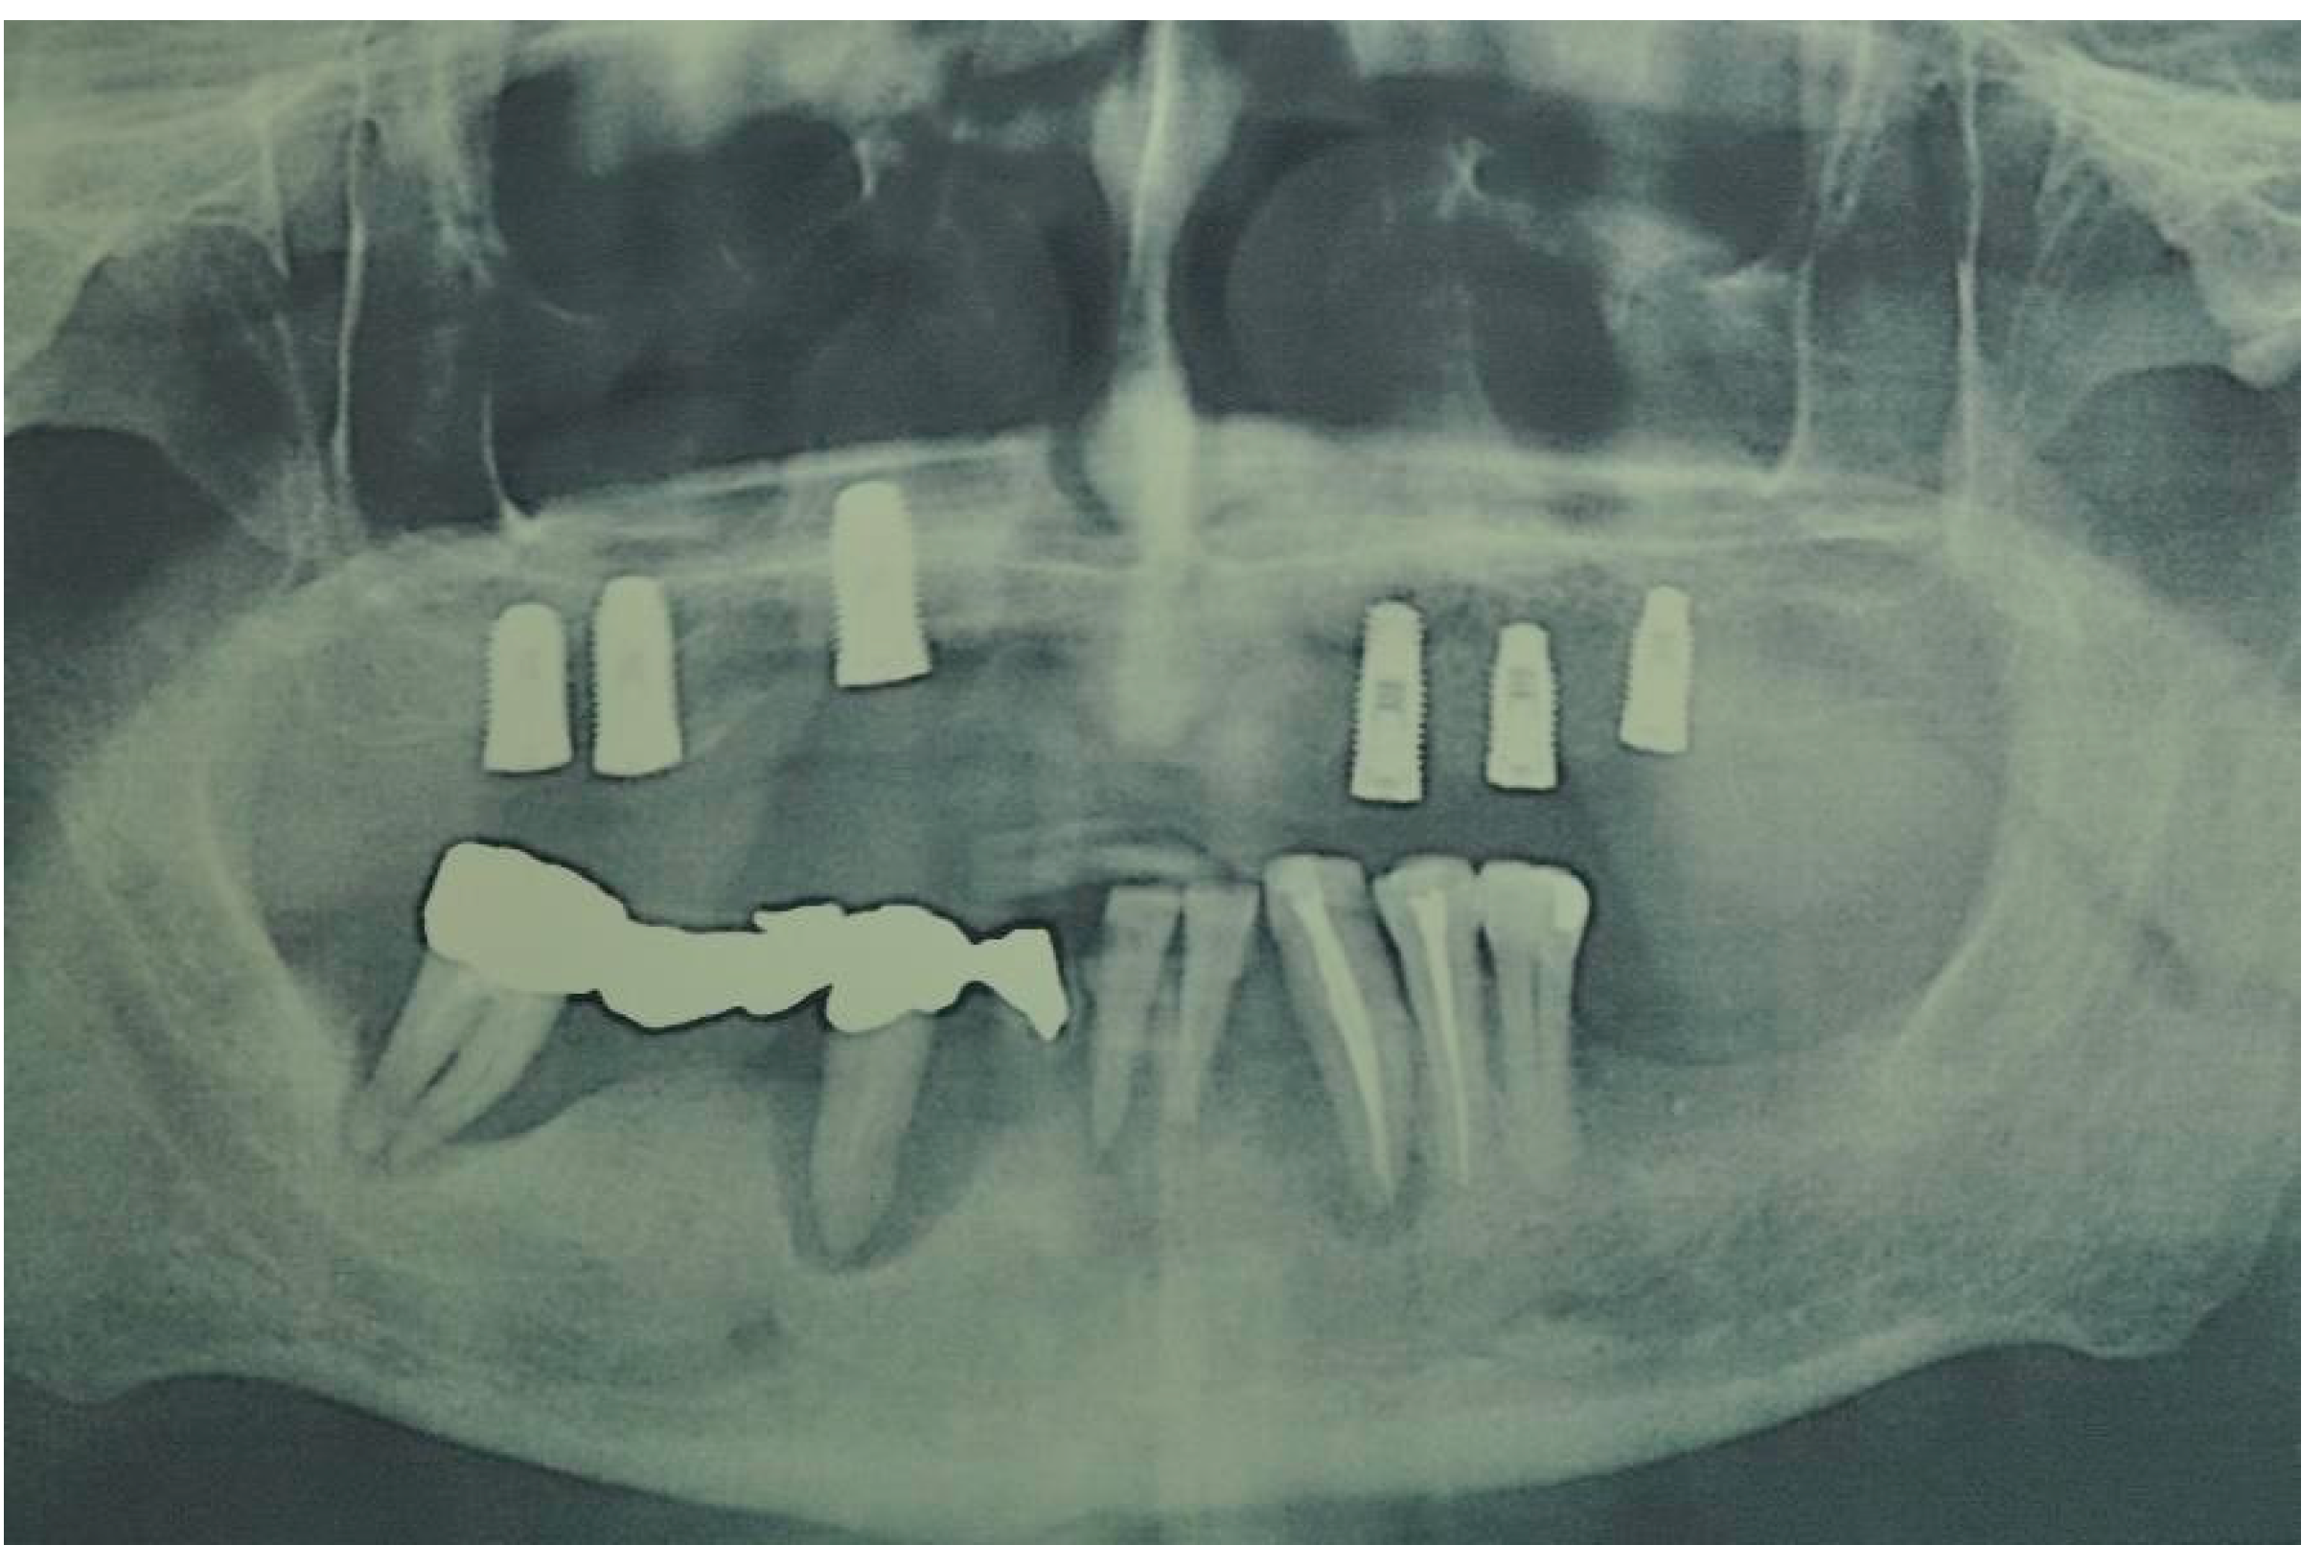

| Flanagan D. et al. [23] | J Oral Implantol | 2015 | clinical and radiographic: full-mouth radiographic series, panoramic and a bimaxillary cone beam computerized scan and mounted study casts | -One patient | Subject of 34 yo male; severely carious teeth and associated chronic abscesses (kidney transplant delayed) Comorbidities: IgA nephropathy, tabagism, hypertension and secondary hyperparathyroidism. Hemodialysis three times weekly. Ph. Therapy: Nephrocaps vitamin (B) supplement, amlodepine, besylate, cinacalcet, metoprolol, paroxetine. Bilateral compound ulnar and radial fractures, 2 blood transfusions. | Successfully treated with dental implant-supported fixed prostheses: fixed bimaxillary porcelain fused to metal implant-supported complete dentures |

| Hernández G. et al. [26] | Clin Oral Impl Res | 2019 | AI, MCI and TP reduction in mineral density of the cortical and trabecular bone in CRF patients and more severely in patients under haemodialysis compared to peritoneal dialysis | 1 IF in T | Mean follow-up of 116.8 months range from 84 to 192 months) | Renal transplant patients, are subjected pharmacological immunosuppression therapy |

| Flanagan D. et al. [23] | J Oral Implantol | 2015 | -Implant treatment for patients with IgA nephropathy (secondary hyperparathyroidism and osteodystrophy) may be successful. -Appropriate calcium therapy is important serum calcium to prevent inappropriate bone remodeling | 2 years | Long-term dialysis patient with end-stage renal disease (ESRD)also referred to as chronic kidney disease (CKD) due to IgA nephropathy complicated by severe secondary hyperparathyroidism and renal osteodystrophy | |